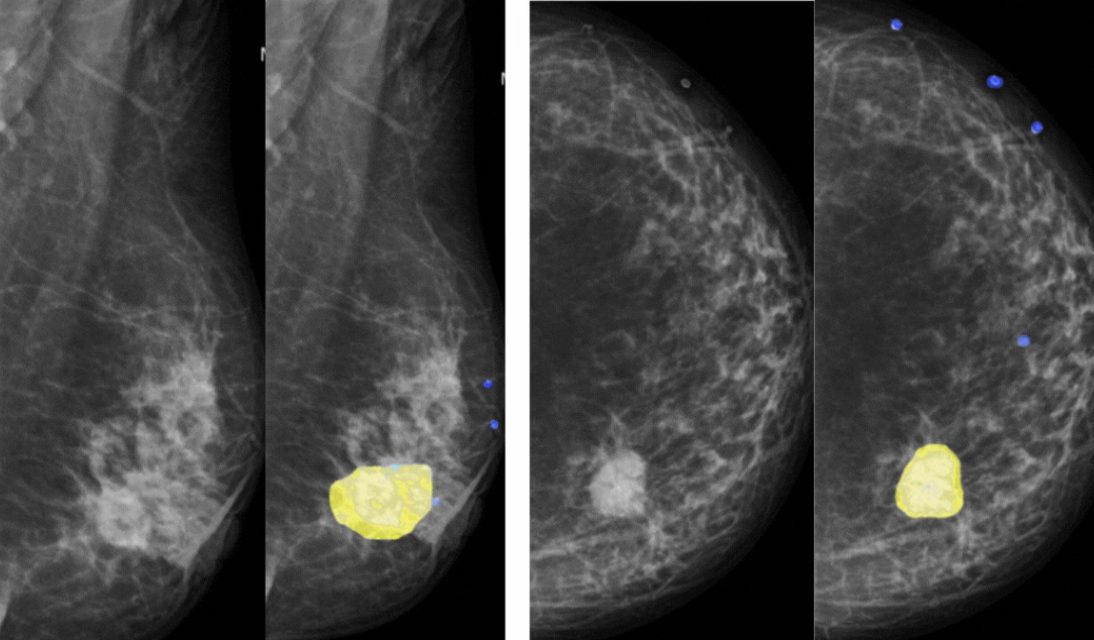

Inteligência Artificial para mamografia

A análise de câncer de mama implica na inspeção de mamografias para detectar lesões e tumores.

Com recursos especializados para essa modalidade de exame, a inteligência artificial pode realizar a segmentação automática de massa mamária mostrando a evolução constante nas análises de mamografia e sugerindo achados mamários com classificação de densidade e malignidade das lesões (BiRads). Recursos como esse também podem ajudar na triagem, sinalizando a prioridade no atendimento.